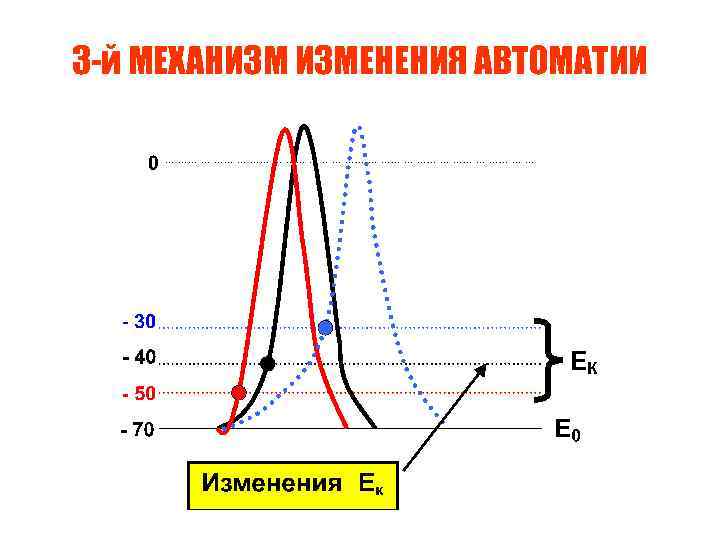

3 -й МЕХАНИЗМ ИЗМЕНЕНИЯ АВТОМАТИИ

3 -й МЕХАНИЗМ ИЗМЕНЕНИЯ АВТОМАТИИ